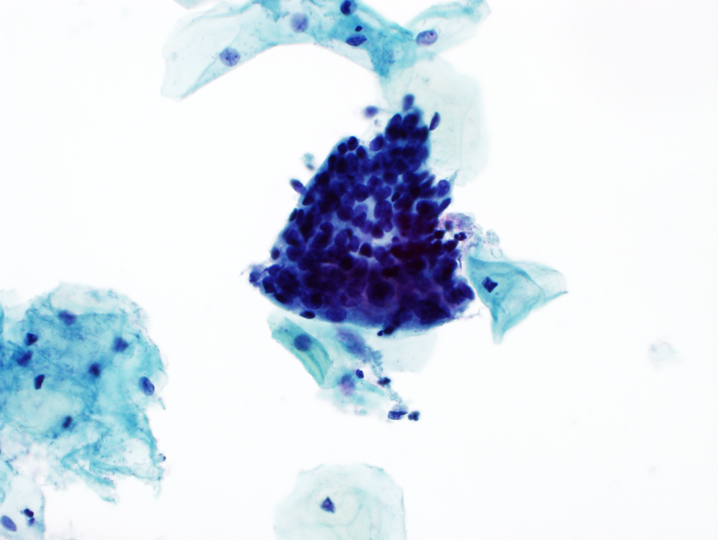

- Atypical endocervical cells, NOS

- Cells occur in sheets and strips with some cell crowding, nuclear overlap or pseudostratification

- Nuclear enlargement and increased N:C ratio

- Anisonucleosis

- Mild nuclear hyperchromasia and chromatin irregularities

- Occasional nucleoli

- Rare mitotic figures

- Distinct cell borders

- Atypical endocervical cells, NOS

Cytology images